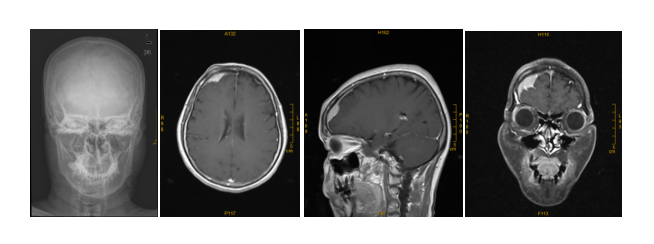

果然,头颅MRI有了新发现:Z女士右侧大脑额叶长了一个肿物,最大层面大小约2.7x2.2x2.6cm,增强扫描明显均匀强化,可见“脑膜尾征”,相邻右侧额叶受压并少许脑水肿。

根据影像学所见,这个头皮肿物可能是脑膜瘤侵蚀颅骨的结果,初步诊断Z女士是“脑膜瘤”。

头颅X线没看到骨瘤,但头颅MRI发现右侧大脑额叶肿物